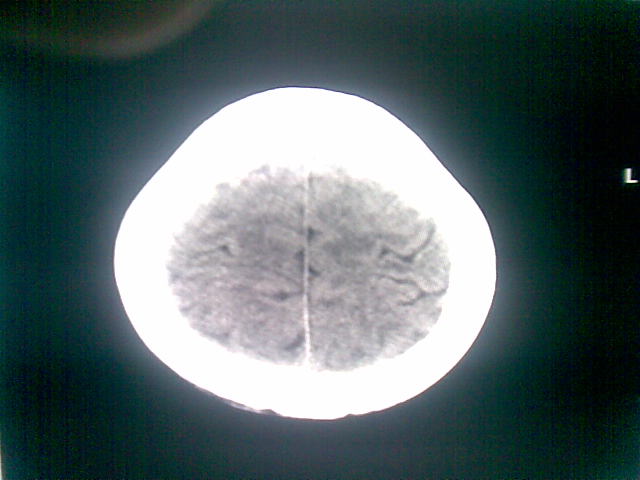

以下是引用随光逐影在2010-1-5 16:32:00的发言:[br]1)鞍上池囊性占位性病变,不排除蛛网膜囊肿可能;建议行mri检查。2)脑积水。

以下是引用yangyang2000在2010-1-5 20:41:00的发言:[br])鞍上池囊性占位性病变,不排除蛛网膜囊肿可能;建议行mri检查。2)脑积水

以下是引用yangyudong333在2010-1-5 21:28:00的发言:[br]1)鞍上池囊性占位性病变,不排除蛛网膜囊肿可能;建议行mri检查。2)脑积水。